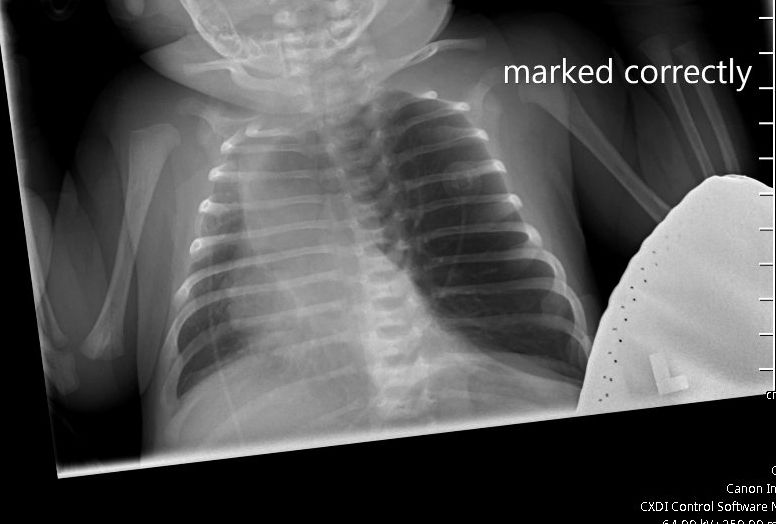

Can you diagnose this patient?